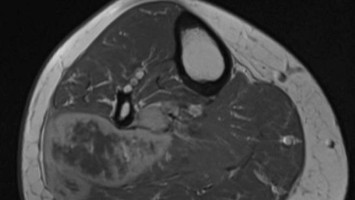

Schmerz in der unteren Extremität nach einer Laparoskopie

Eine 49-jährige Patientin stellt sich einen Tag nach einer Laparoskopie bei Ihnen vor. Sie klagt über Schmerzen in der rechten Wade, mit einhergehender Rötung und Schwellung. Was hat die Patientin?